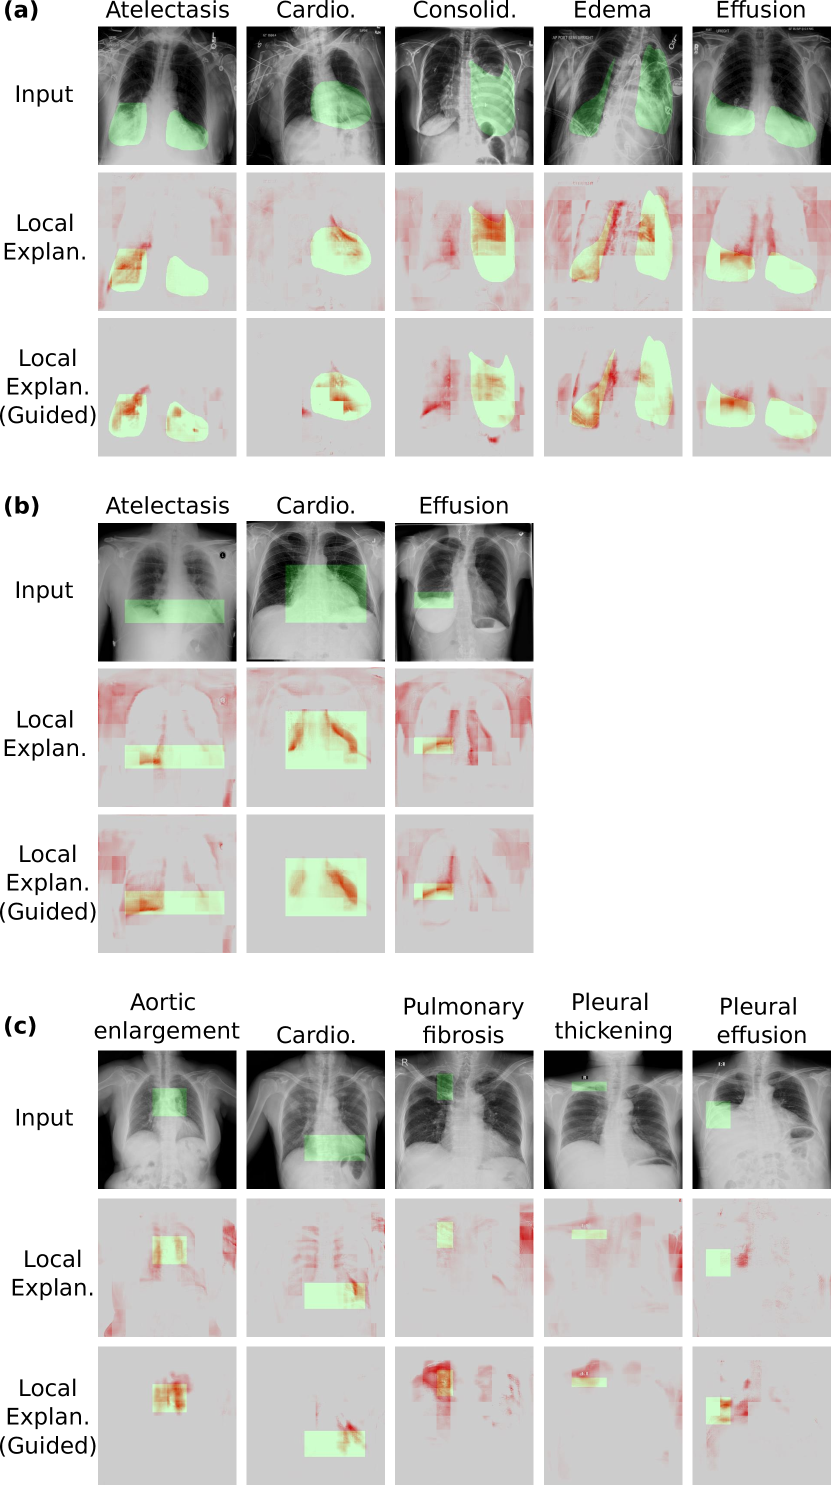

We derived local explanation for Attri-Net using the weighted attribution maps as detailed in Sec. 3.6.1 and compared our local explanations with those from B-cos ResNet50 and five post-hoc methods that explain the prediction for the black-box ResNet50 model.

4.4.2 Qualitative Analysis of Explanations

The qualitative examination of example explanations supported the quantitative results. Attri-Net was capable of generating local explanations that effectively emphasize the anatomical regions associated with the respective classes (see Fig. 6 for a representative example from the ChestX-ray8 dataset). Besides, explanations for highly confident predictions, such as cardiomegaly, exhibited a more pronounced disease effect compared to negative predictions like Edema. Furthermore, the attributions for different classes were clearly distinct, each highlighting different anatomical areas. In contrast, it was challenging to understand the explanations from other post-hoc methods and the inherently interpretable baseline, B-cos ResNet50. For instance, explanations derived from Guided Backpropagation and B-cos ResNet50 were very noisy and hard to interpret. The explanations from the counterfactual-based Gifsplanation approach were easier to interpret, yet they consistently emphasized similar regions for different diseases. More examples from the CheXpert and VinDr-CXR datasets can be found in the supplementary materials (Sec. C).

We further examined Attri-Net explanations on images with pixel-wise ground truth annotations (Fig. 11) and observed that after adding pseudo-guidance to the model, the local explanations produced by Attri-Net better matched the areas where the pathologies are located, which was consistent with the high disease sensitivity in our quantitative evaluation. This suggested that incorporating guidance assisted the model in being “right for the right reason.”